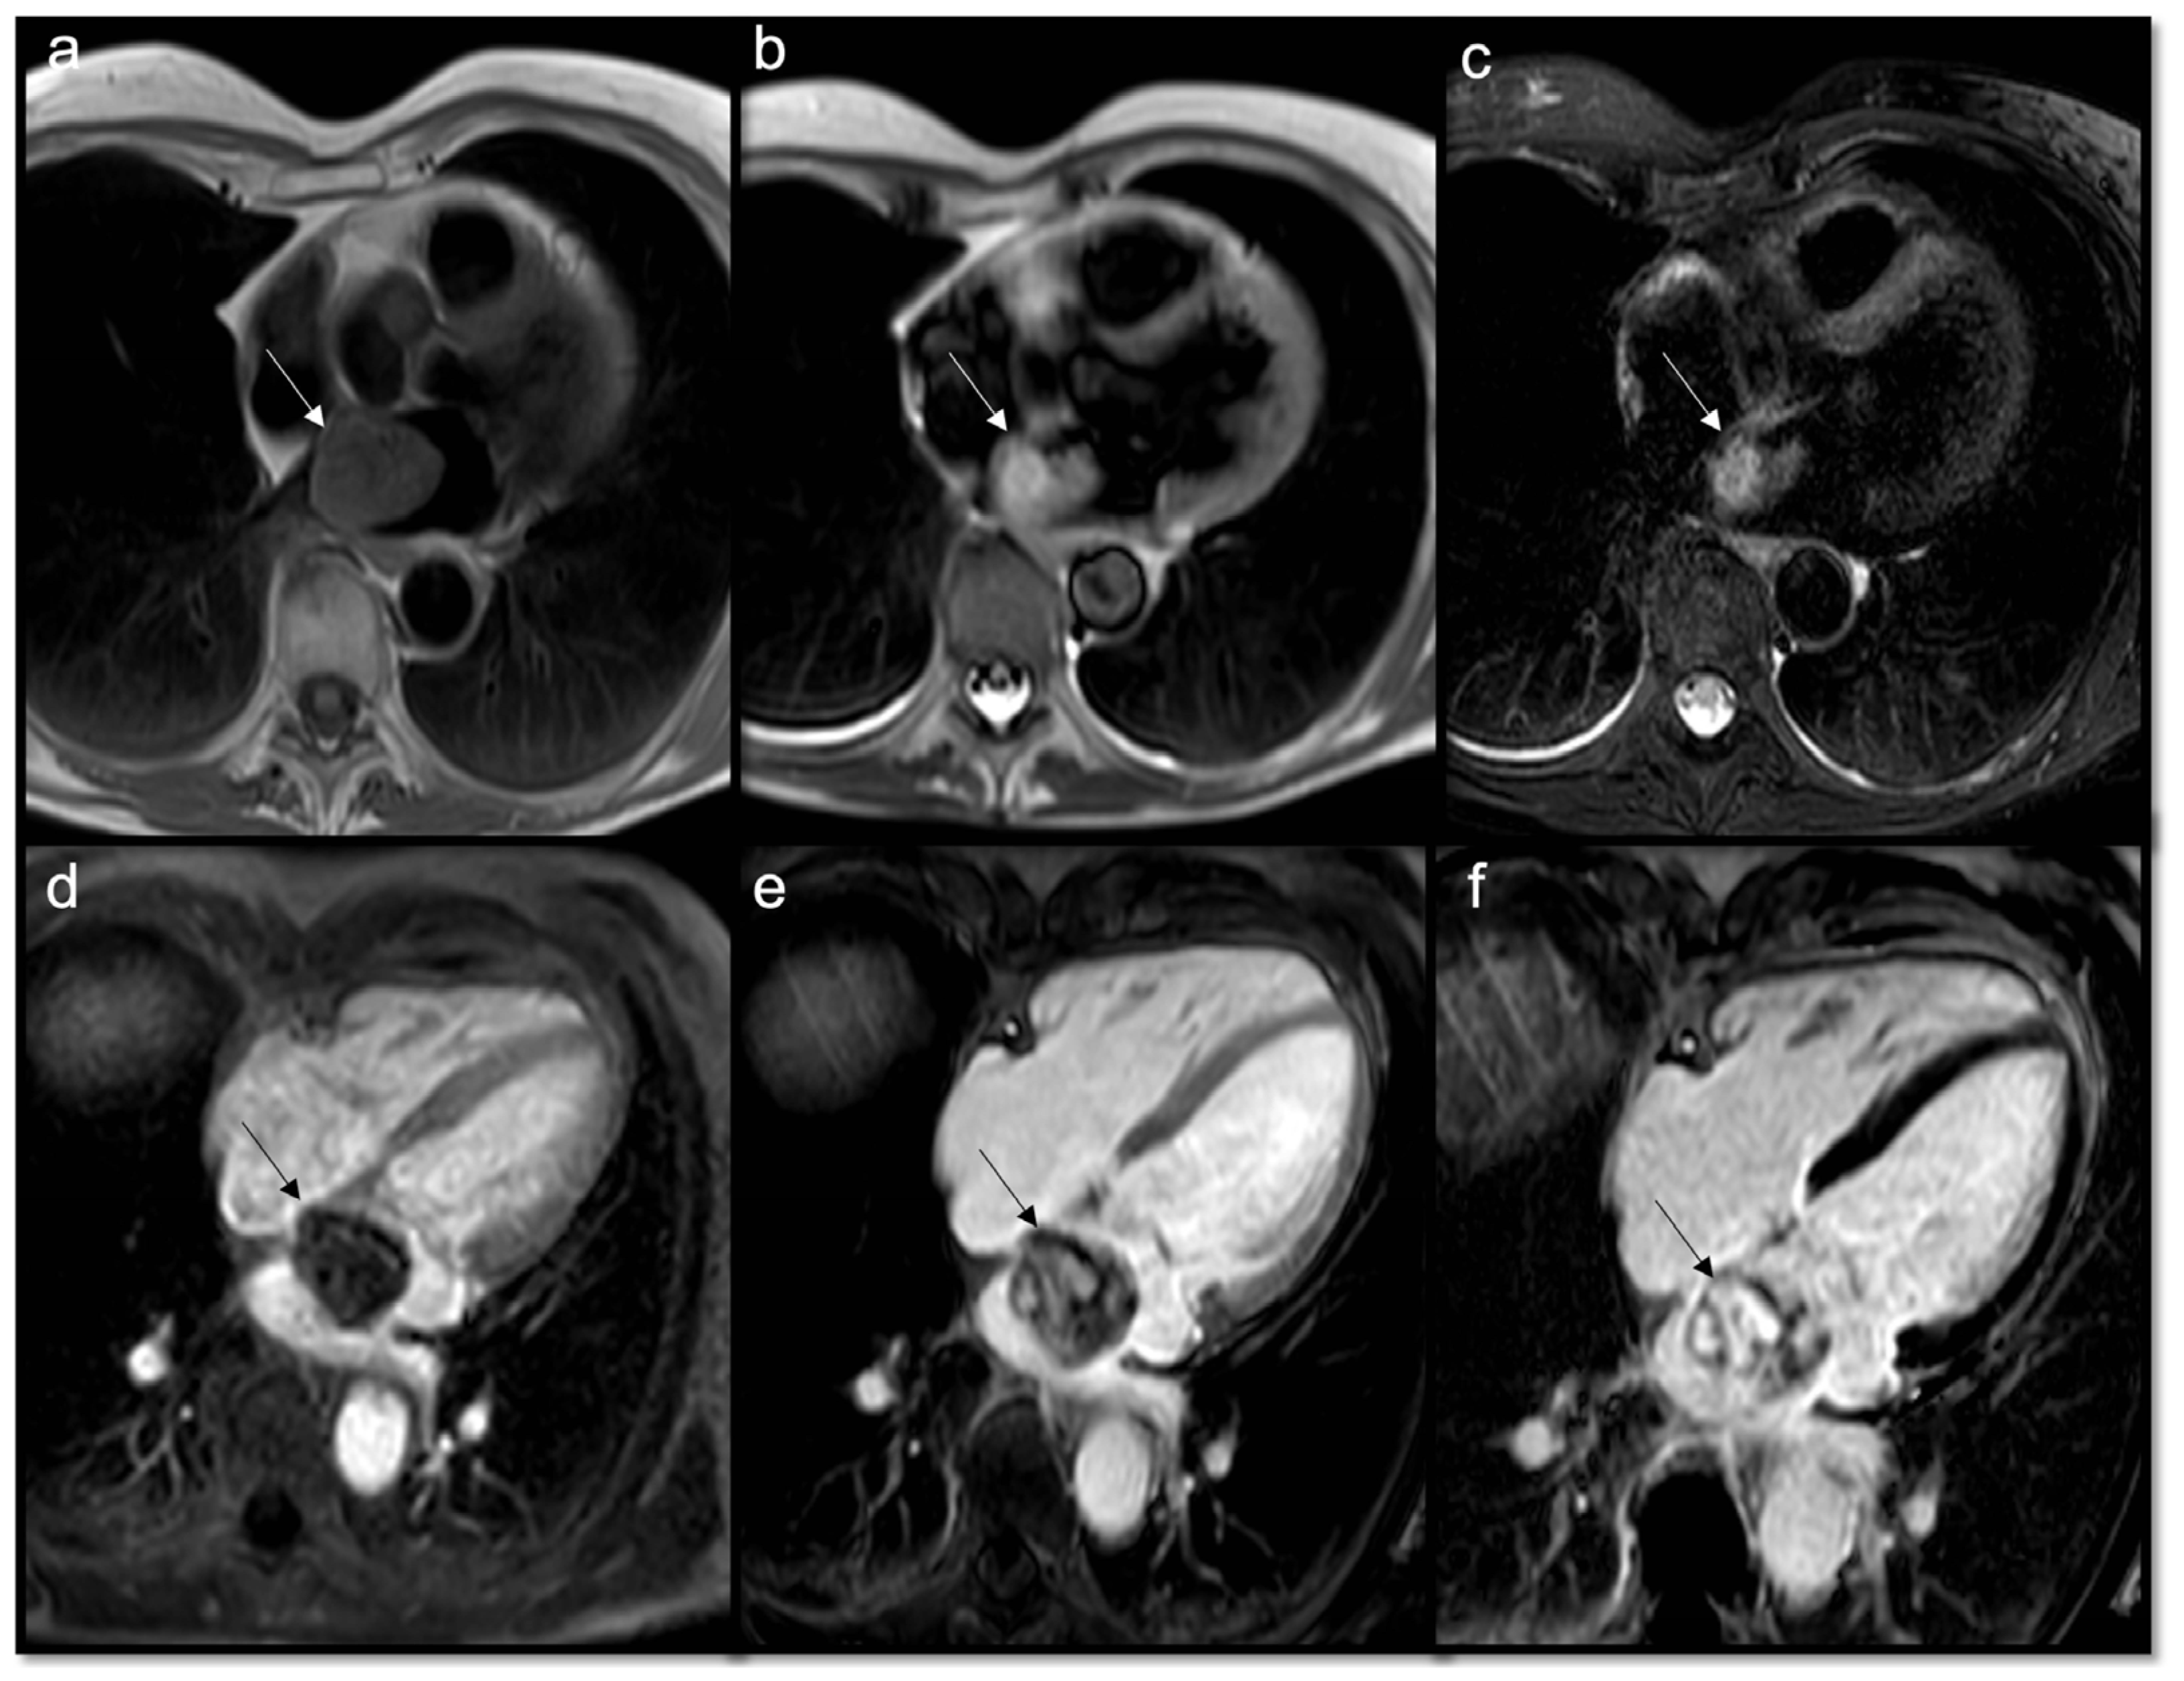

7.2. Black Blood Imaging

7.2.1. T2-Weighted Triple-Inversion Recovery Images

- High signal: fluid, myxomatous components

- Low signal: calcific components

- To recognize fluid content such as a pericardial cyst or myocardial cyst (Figure 3)

- To assess for edema or necrosis in the mass.

7.2.2. T1-Weighted Double-Inversion Recovery Images

- To achieve a better anatomic definition than T2w ones

- High signal: lipid content, melanin, blood catabolites (methemoglobin)

- Low signal: indicates fibrosis